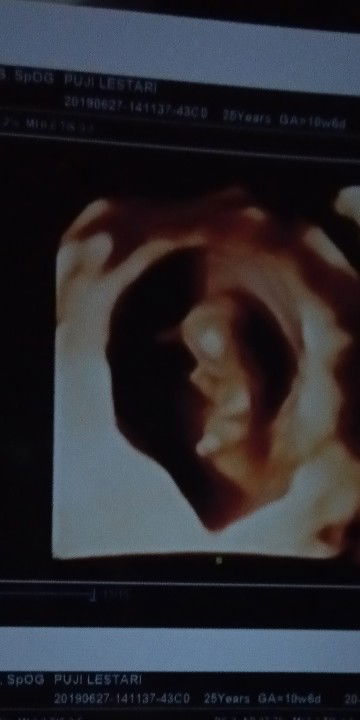

bunda waktu hamil ada yang makan sate gak ? aku lagi hamil 12 w , pengen banget makan sate, apalagi sate taichan. tp katanya gak boleh makan sate kan ?